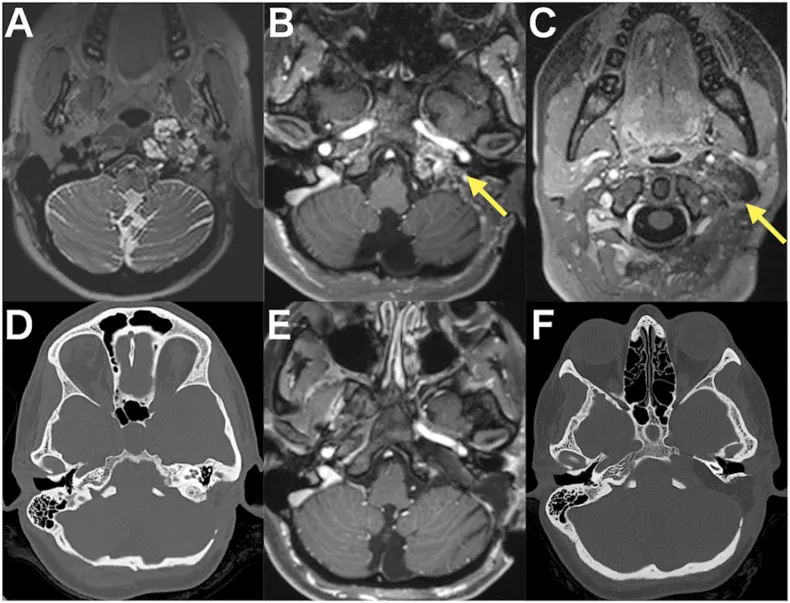

图1、六个时间点的影像记录:依次是术前T2像、术前增强T1两个切面显示肿瘤从岩尖到颈部的范围、术前CT骨窗显示岩骨被侵蚀的样子、术后增强T1确认近全切除、以及术后CT显示岩骨已被磨除的范围。

患者是位29岁女性,左侧颈静脉孔区长了脑膜瘤,而且此前已经在别的医院动过两次刀。第一次切了一部分;第二次从侧前方进去做根治,病理出来发现是一种带乳头状和横纹肌样特征的罕见亚型,恶性程度比普通脑膜瘤高一些。手术留了一点残余在颈静脉孔深处,术后跟进了质子束放疗。本以为稳住了,结果三年过去,肿瘤卷土重来,患者开始出现吞咽困难和头痛。复查影像发现,肿瘤已经主要吃进了岩骨,前缘一直顶到了颈椎C1、C2的位置。

术后片子上肿瘤近全切除,岩骨被磨掉了不少,但底下的关键骨头结构都保住了。患者醒来没有任何神经损伤,听力完好,吞咽困难做了一段时间康复训练后也有改善,第11天出院回家。病理确诊是脑膜瘤。出院后继续做了质子治疗,随访一年一切正常。